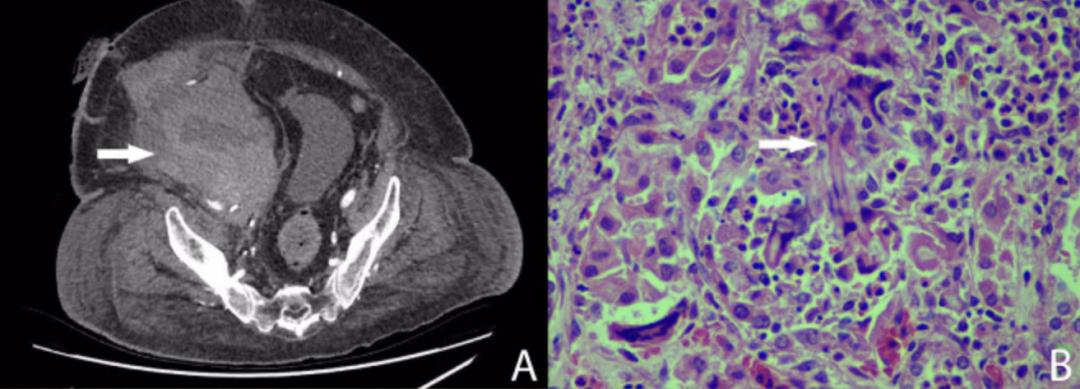

第22天,患者再次出现低血压。CT血管造影显示肾动脉和髂外动脉吻合口处有活动性出血(图A);患者接受经皮支架植入术,血液外渗得以解决。

移植物的组织病理学显示为肿大、苍白肾脏,有几个直径达5毫米的白斑。显微镜检查显示炎症区域含有嗜中性粒细胞和多核巨细胞,包围真菌菌丝和分生孢子(图B)。荧光原位杂交的真菌筛查呈阳性,酵母菌筛查呈阴性。肾动脉、肾静脉、肾盂和输尿管未发现真菌。然而,肾动脉样本培养呈黄曲霉菌(Aspergillus flavus)阳性。患者开始口服伏立康唑(400mg Bid负荷剂量,随后200mg Bid),并在第31天接受进一步手术,以移除支架和供体主动脉补片,随后的支架和补片培养均为黄曲霉菌和万古霉素耐药肠球菌(VRE)阳性。为了保护右腿的动脉供应,接受股-股旁路手术。加入利奈唑胺以覆盖VRE,伏立康唑改为静脉给药,并进行治疗药物监测。